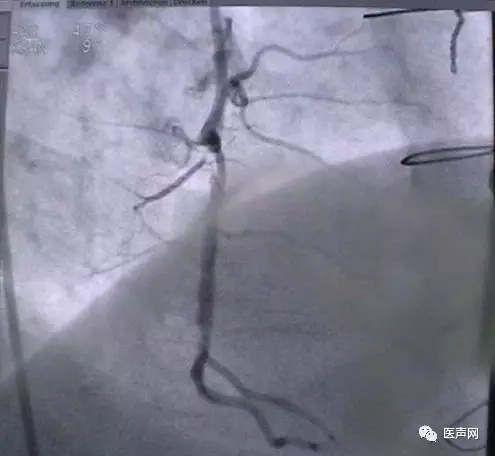

病例1: 冠脉搭桥术后,静脉桥CTO(CABG, VB-CTO)

箭头所示为第3个吻合点

(pre-PCI)

VB-对角支(jump)---LCX(jump)-PDA远端,第一个吻合以下完全阻断。

· 导引导管非常深置(Very very deep seating)(本例GC达CTO 第一吻合口前)(这是Dr. Lauer常用一招)

· 对侧造影

· 硬导丝(走得很远, 达PDA)

· 微导管,OTW 球囊.

当打通后,发生室速,电复律---出现无复流---室速---植入支架(TAXUS Liberte)

当导引导管非常深置(very very deep seating)时,你可以想象支持力有多大,永远不要忘记他做RCA-CTO时导引导管深插到RCA中段的例子。此病例实际上PDA未能开通,在6月28日 Dr. Lauer终于用类似方法打通了PDA。